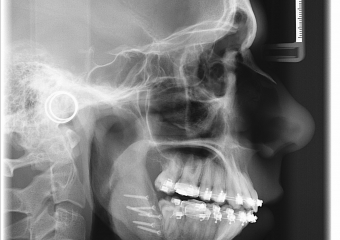

Telerradiografia perfil inicial - Clínica Cliniface

Telerradiografia perfil inicial